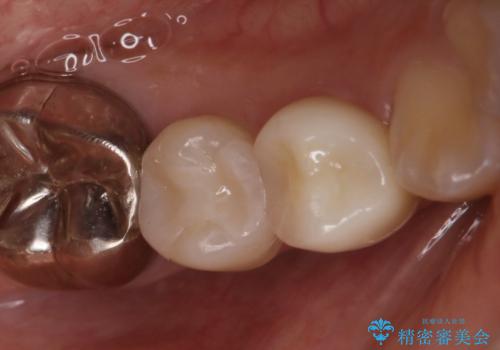

海外に引っ越す予定があり、見ため(審美性)強度ともに良い被せ物を希望されたため、セラミックインレーにて治療を行いました。

一部歯に保険治療で使用されている材料が劣化していたため、う蝕と一緒に取り除いて劣化の少ないセラミックに置き換わりました。